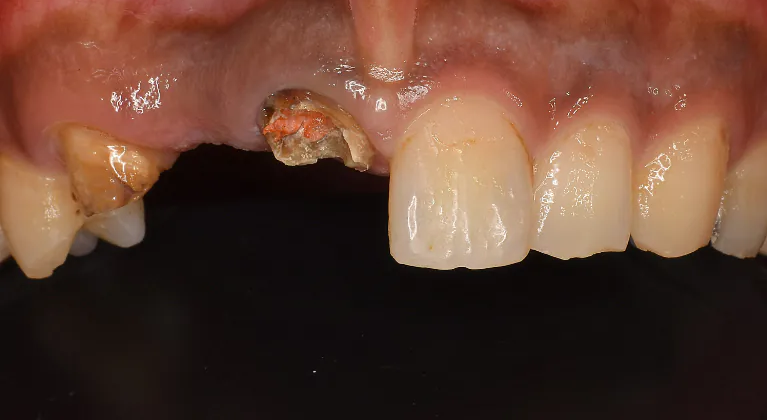

Case6

術前

術中

術後

| 治療名 | 抜歯即時インプラントによる審美的回復症例 |

| 治療説明 |

歯の根が割れてしまったことにより、抜歯が必要となった症例です。 インプラント周囲の骨の一部に吸収が見られたため、小規模な骨造成(GBR)を併用しました。 |

| 治療回数・期間 | 約3ヶ月 |

| 副作用とリスク | ・入れ歯や従来のブリッジに比べて治療期間が長くなることがあります。 ・骨造成を伴う場合、さらに期間が延びることがあります。 ・インプラント手術後には一時的に痛み、腫れ、出血、違和感などが生じることがありますが、多くは数日〜1週間程度で治まります。 |

| 料金(税込) | 小規模GBR:110,000円 インプラント一次手術:220,000円 二次手術:55,000円 上部構造〈セラミック〉:165,000円 合計:550,000円 |